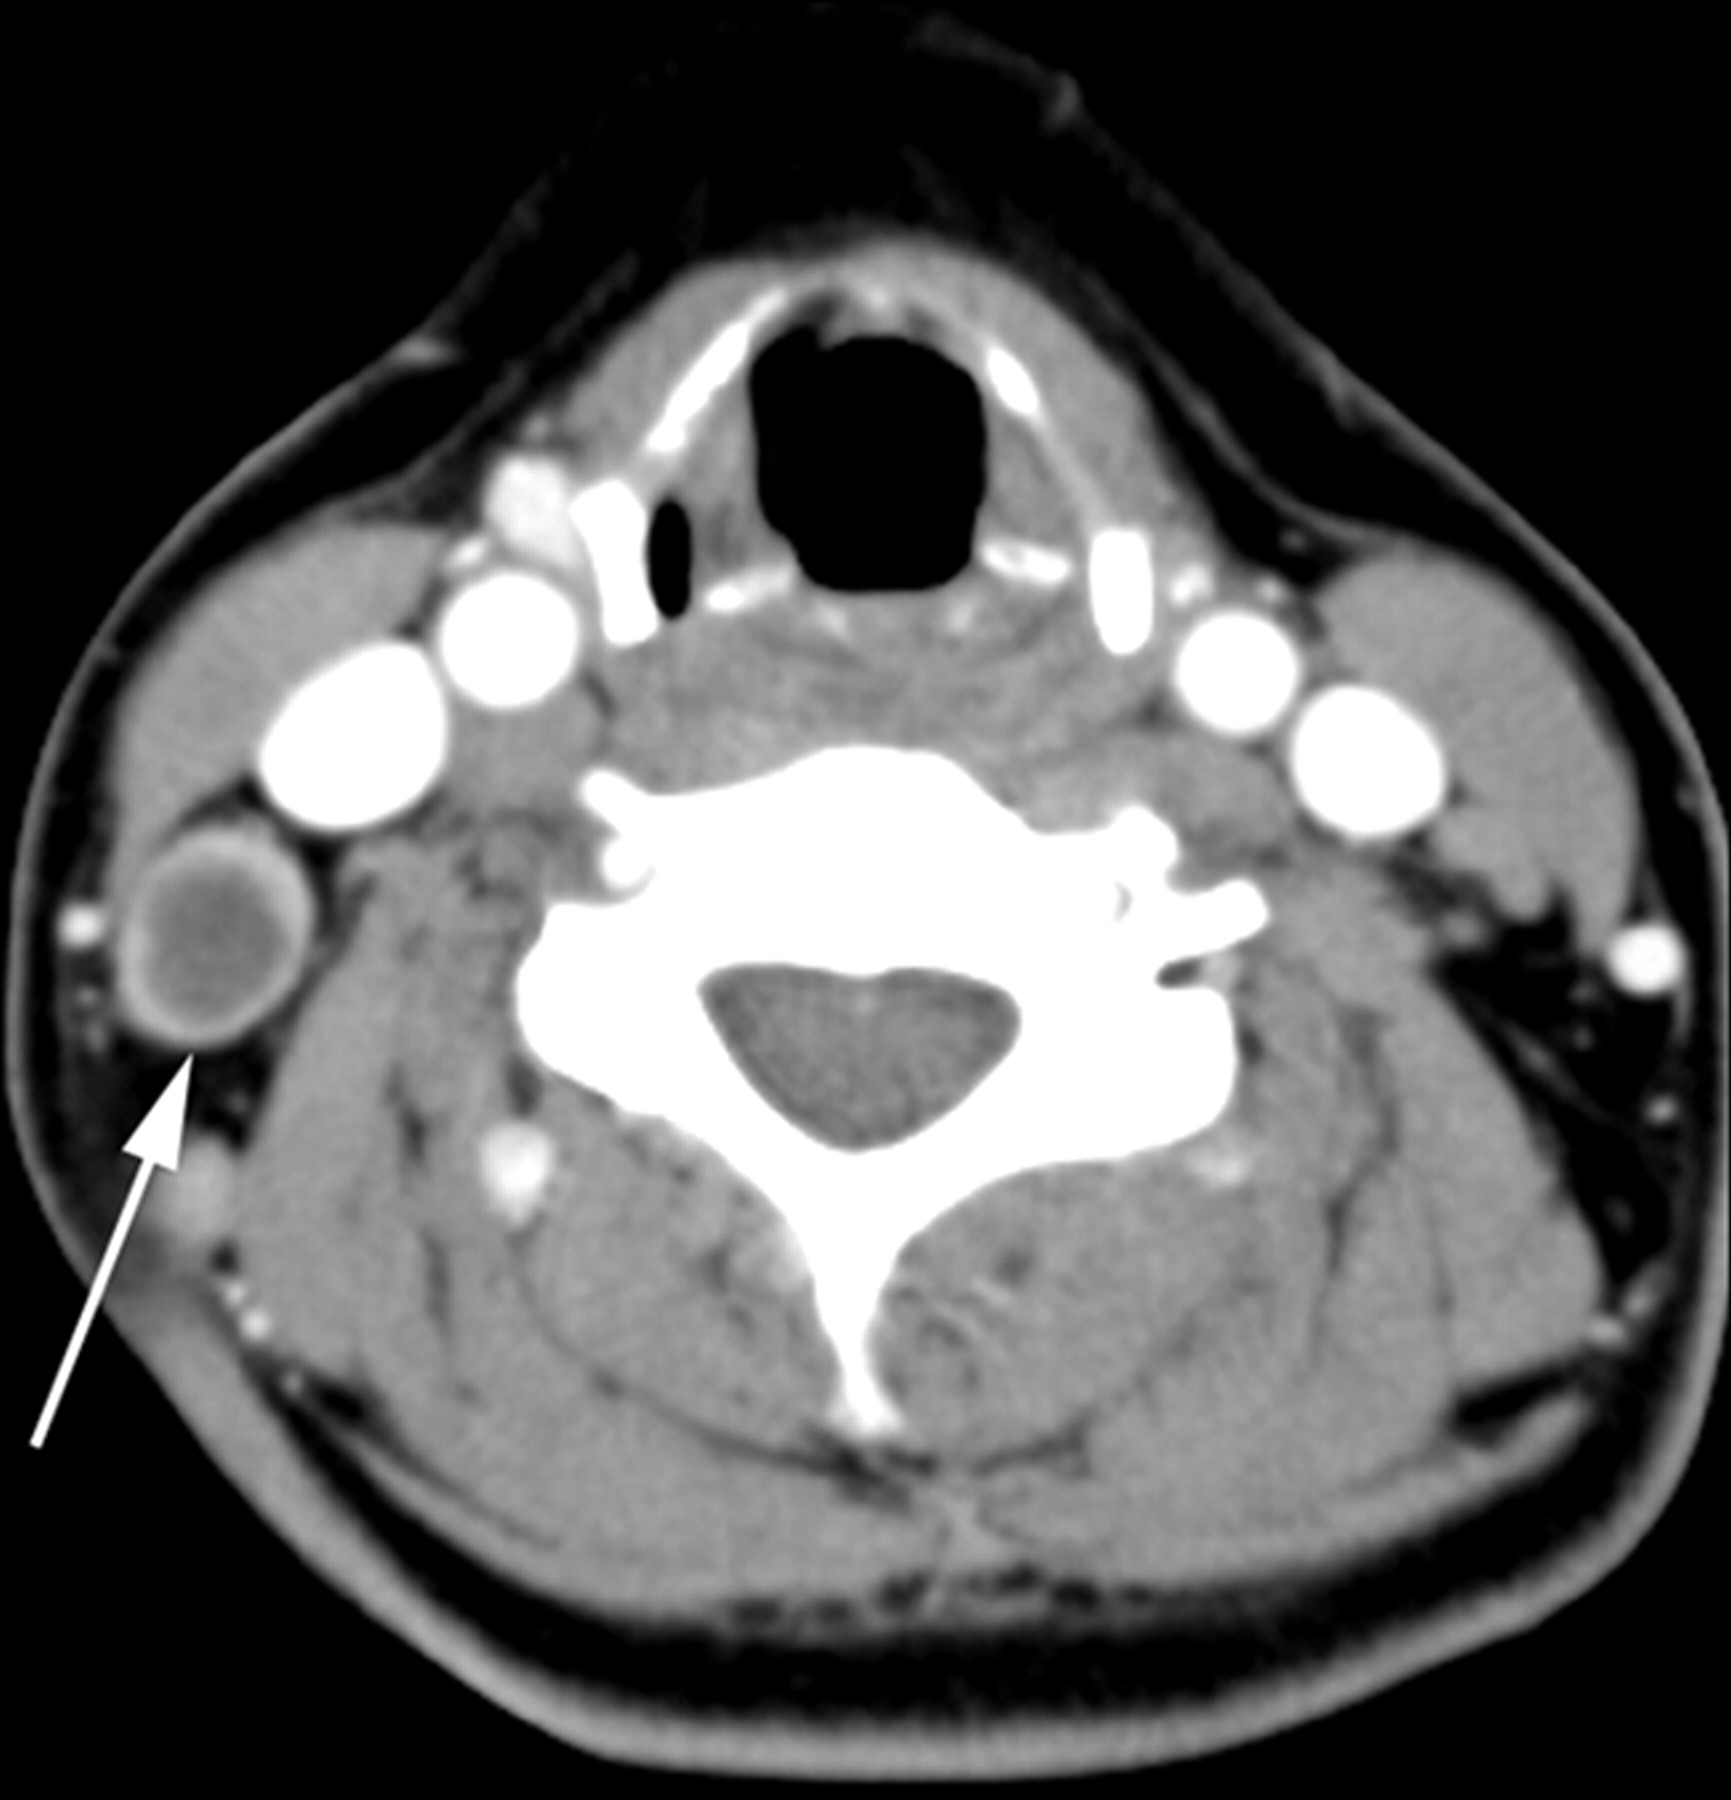

Understand the causes, symptoms, and treatment options for a cyst of the stomach. Learn how medical professionals diagnose gastric cysts, differentiate them from other abdominal growths, and when surgical intervention or endoscopic removal becomes necessary for your digestive health. Stay informed about these rare stomach lesions and the latest clinical approaches for effective management and long-term recovery.

Read full article: Cyst Of Stomach